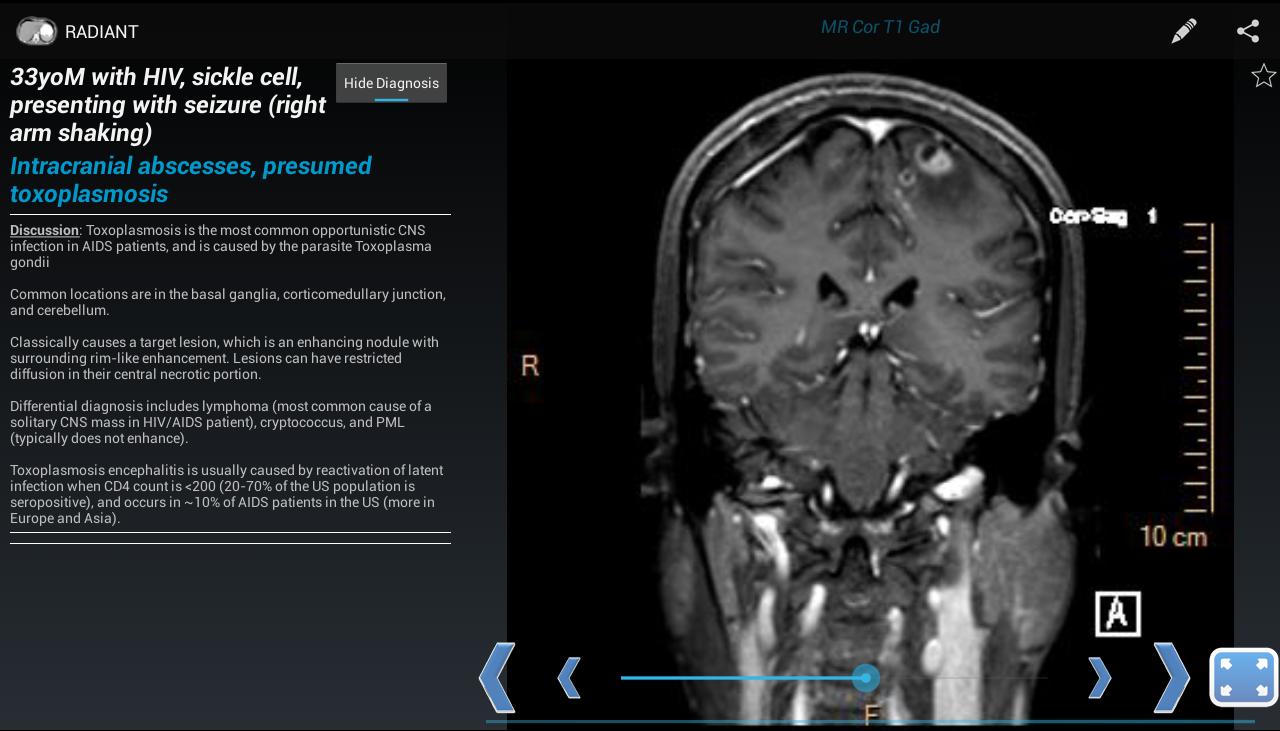

Com o Radiant, você pode criar casos mostrando raios-X, ultrassom, CT, ressonância magnética ou qualquer outra modalidade de imagem. É uma ótima maneira de aprender radiografias de tórax, anatomia normal e processos de doenças comuns, usando imagens médicas de diagnóstico reais e de alta qualidade.